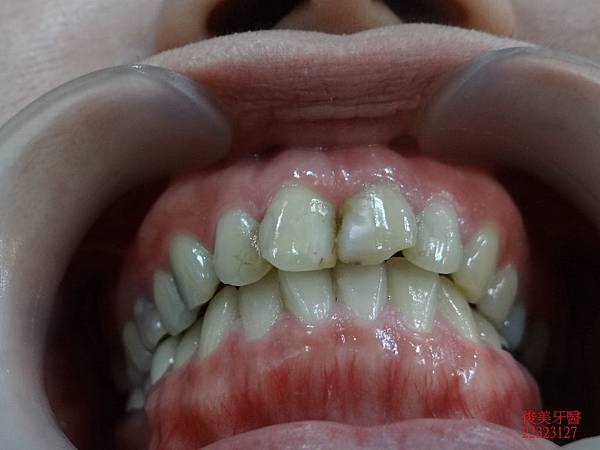

側邊咬合。

上排牙齒已有延長的現象,牙縫更容易塞東西,且沒有咀嚼功能。